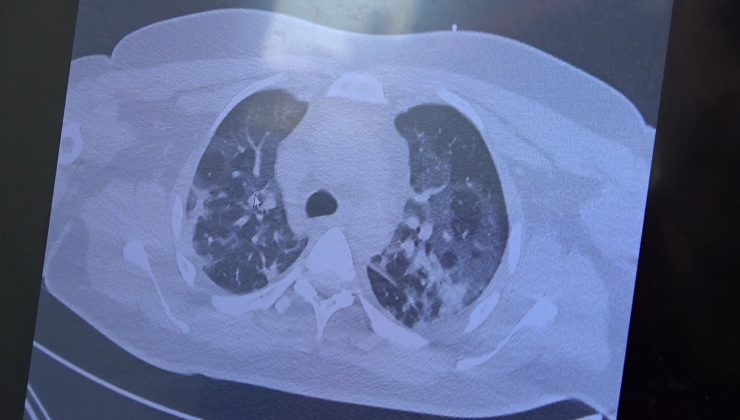

Türkiye’de Kovid-19 vaka sayıları tırmanışa geçerken hasta profili ise değişmeye başladı. Göğüs Hastalıkları Uzmanı Prof. Dr. Şevket Özkaya, aşısız gençlerin çok ciddi akciğer tutulumları ile geldiğine dikkat çekerek, kapanmaya başlayan kovid servislerinin genç hastalarla dolmaya başladığını söyledi.

Kovid-19 vakaları yeniden bir artış eğilimine girerken kapanan kovid servisleri aşısız gençlerle tekrardan hareketlenmeye başladı. Binlerce kovid hastasını iyileştirmiş VM Medical Park Samsun Hastanesi Göğüs Hastalıkları Kliniği’nden Prof. Dr. Şevket Özkaya, vaka sayılarının düşmesinden dolayı insanların hastalığı bilinç altına atarak kontrolsüz sosyal hayat yaşadıklarını belirtti. Aşı ve delta virüsü ile beraber hasta profilinin değiştiğini ifade eden Prof. Dr. Özkaya, “Deltanın hızlı yayılması sebebiyle gençlerde ve aşı olmayanlarda yaygın bir şekilde hastaneye yatışlar var. Kapanan çoğu kovid servisleri tekrar açılmaya başladı. Hasta profilleri de artık 20 ile 30 yaş arasındaki bireylere kaymaya başladı. Bu yüzden son 2 ayda hastalığın azalmasıyla insanlar hastalığı hem inkar ediyorlar hem de aşı endişesini yaşıyorlar. Bu inkara dokunmamız lazım. Bu hastalık gençleri etkiliyor. Eskisi gibi 65 yaş üstü vatandaşlar riskli diyemiyoruz artık. Özellikle aşı olmayan gençlerimiz risk altında ve yatan hastalarımız gençlerden oluşuyor” dedi.

“Geçmişte hastaların yatacak yer bulamadığı dönemdeki hasta profilini görmeye başladık”

Gelenlerin çok ciddi akciğer tutulumların olduğuna dikkat çeken Özkaya, “Geçtiğimiz sene aşı bağışıklık oluşturacak mı diye herkesin endişesi vardı. Doğal olmayan bir virüse karşı geliştirilen aşı gerçekten insanları koruyacak mı diye hepimizi endişeliydik ama aşı geldikten sonra ölüm oranlarının belirgin şekilde azaldığını görünce aşının gerçekten işe yaradığını gördük. Son 2 ayda vakalar azalınca insanları hastalığı bilinç altlarına atarak kontrolsüz sosyal hayatlarına devam ettiler. Bunun sonucunda geçmişte hastaların yatacak yer bulamadığı dönemdeki hasta profilini görmeye başladık. Gelenler ciddi akciğer tutulumları ile geliyor” diye konuştu.

“Aşı olunması şart”

Gençlerin akciğer tomografilerini inceleyen Özkaya, “İki vaka örneği hakkında bilgi vermek istiyorum. İnsanlara bu işin bitmediğini anlatmamız lazım. 30 yaşında aşı olmamış bir hastamızın filminde çok yaygın akciğer hasarı var. Şu an kendisi yoğun bakımda tedavi alıyor. Öte yandan 25 yaşında bir hastamız var. İki doz kovid aşısını da olmamış. Ciddi akciğer tutulumları var. Çok ciddi solunum sıkıntısı ile kovid servisinde yatıyor. Şu an hasta profilimizin büyük bir kısmını bu durum oluşturuyor” ifadelerini kullandı.